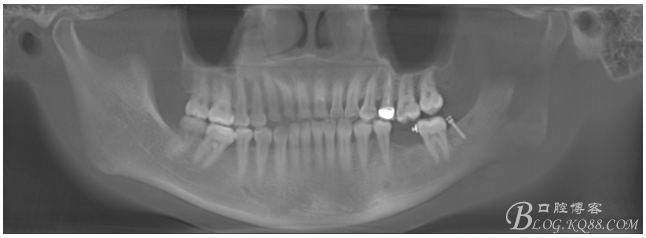

植入5.0X10mm植體

術(shù)后CT片

注:此時(shí)并不能拆除37遠(yuǎn)中支抗釘,需等待取模型時(shí)再拆除支抗釘和舌側(cè)扣,防止37傾斜復(fù)發(fā)。